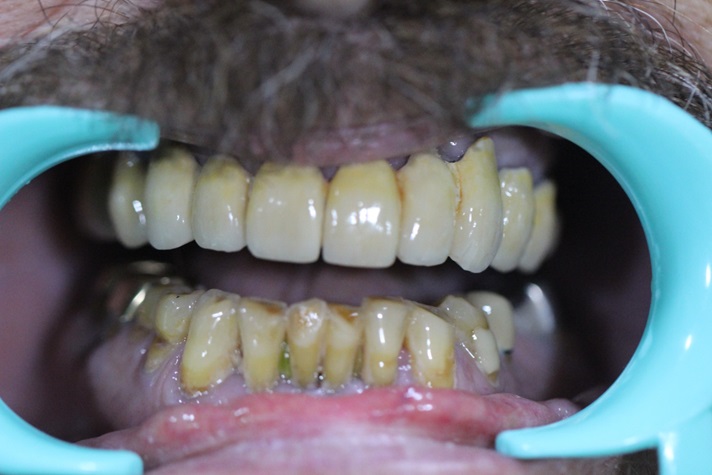

This case report show the successful All on 6 dental implantation using Alpha Dent implants.